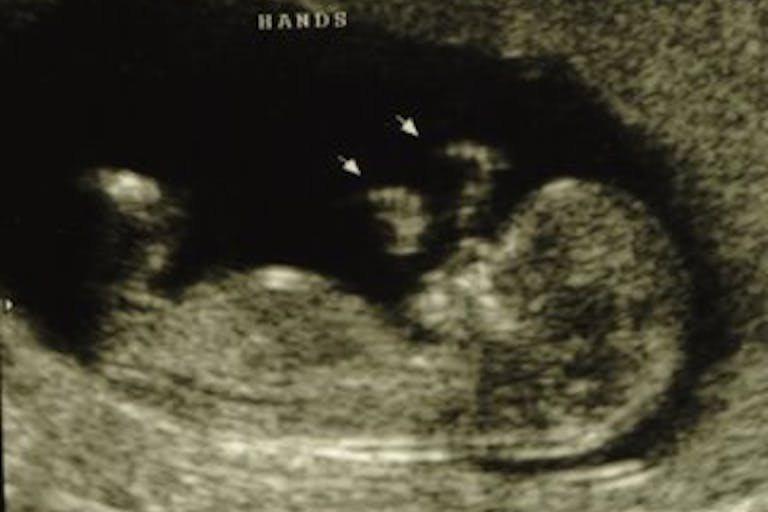

“Sometimes we lied. A girl might ask what her baby was like at a certain point in the pregnancy: Was it a baby yet? Even as early as 12 weeks a baby is totally formed, he has fingerprints, turns his head, fans his toes, feels pain. But we would say ‘It’s not a baby yet. It’s just tissue, like a clot.’(1)

While it has not been scientifically determined that the baby can process pain at 12 weeks the way an older child can, you can see a video of a 12-week-old baby responding to touch here, on the Endowment for Human Development website, which is not affiliated with the pro-life movement.